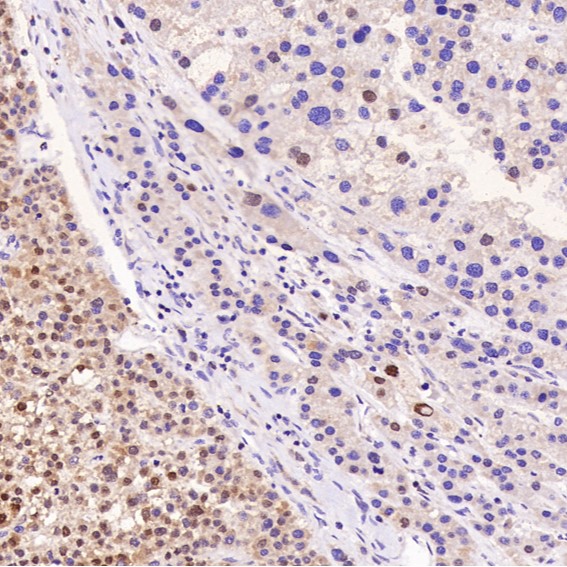

Immunohistochemical analysis of paraffin-embedded Human liver cancer, using the Antibody.

Immunohistochemical analysis of paraffin-embedded Human liver cancer, using the Antibody.